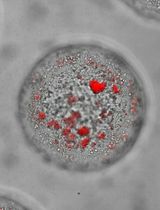

Even though the survival and proliferation stages of cancer cells that have newly settled at a metastatic site are the rate-limiting stages and the most promising targets for drugs, there is a lack of models of the earliest stage of metastasis formation. A method for modeling breast cancer liver metastasis is described here: a stage of transition of a differentiated tumor cell into a cell actively proliferating in a three-dimensional (3D) liver spheroid. Opposite to existing heterocellular 3D models of metastases, the protocol allows modeling the initial stage of liver colonization by metastatic cells, the so-called “micrometastases.” The method includes obtaining a line of fluorescent tumor cells, fluorescence-activated sorting of differentiated cells, preparing a single-cell suspension of liver cells, forming a liver spheroid in an agarose mold, inducing the tumor cell dedifferentiation and proliferation using IL-6, and intravital microscopy of spheroids, with subsequent processing and analysis of fluorescent images in the ImageJ software. The performance of the proposed model was demonstrated using microRNA therapeutics. The ability of a combination of microRNAs to suppress the transition of micrometastasis to macrometastasis in the 3D liver spheroid was confirmed by an immunofluorescent assay of spheroid sections and transcriptome analysis.